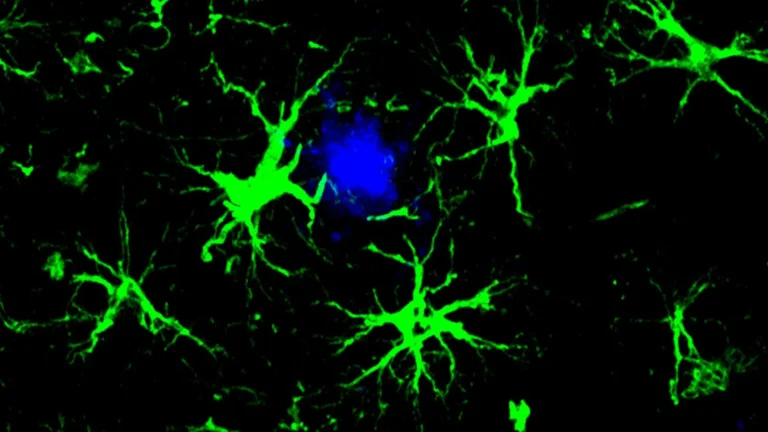

Groundbreaking investigations have illuminated a specific molecular vulnerability within a crucial brain receptor, paving the way for...